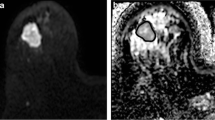

MDpre of responders (0.99 ± 0.27 10−3 mm2/s) was significantly (p = 0.025) lower than MDpre of non-responders (1.46 ± 0.33 10−3 mm2/s) (Figs. 1, 2, 3). Moreover, in the group of patients as a whole (responders and non-responders) PVR significantly correlated (p = 0.01, r = −0.54) with MDpre (Fig. 4). In responders (Fig. 5) MDpost (1.26 ± 0.39 10−3 mm2/s) was significantly (p = 0.024) higher than MDpre (0.99 ± 0.27 10−3 mm2/s) whereas in the small group of non-responders (Fig. 6) MDpost (1.00 ± 0.14 10−3 mm2/s) decreased with respect to MDpre (1.46 ± 0.33 10−3 mm2/s) but not significantly (p > 0.05).

The accuracy of volume and diffusion measurements may become difficult to assess heterogeneous tumours without a clear delineation, such as that depicted in Fig. 2, or tumours with linear/dendritic neoplastic distribution and multicentricity with lesions smaller than resolution of MD maps, although they were not observed in our patients. This could be a limit of MD measurements, especially in monitoring treatment in cases of irregular tumour fragmentation after chemotherapy with small and multifocal neoplastic residuals. Besides, we recognise as a limitation of our study the relatively low number of patients due to the high rate of incomplete MRI examinations. Hence, our results have to be considered as precursors to future studies in larger samples of patients. In this regard, we tentatively tried to infer further analysis from the data reported by Sharma et al. [17] and Pickles et al. [13]. It should be noticed that the study of Sharma and co-workers includes a number of patients (29) comparable with the number of patients included in our study (21). On the other hand, Pickles and co-workers enrolled a smaller number of patients. The data of Sharma and co-workers seem to indicate that in responder patients (PVR > 65%) the mean ADC before treatment is lower compared with non-responder patients (PVR < 65%) but not significantly (p > 0.05, Mann Whitney test). Pickles and co-workers did not measure tumour volume. However, the ADC pre-chemotherapy does not significantly correlate (p > 0.05, Spearman test) with the percentage variation of the longest diameter of the tumour. We think that a comparison between different studies should be performed with caution. Indeed, in our study we measured MD using b-values of 0, 1,000 s/mm2, whereas Sharma et al. [17] and Pickles et al. [13] measured ADC using b-values of 0, 500, 1,000 s/mm2 and 0, 700 s/mm2, respectively. Moreover, for the three studies different MR scanners and acquisition sequences were employed.